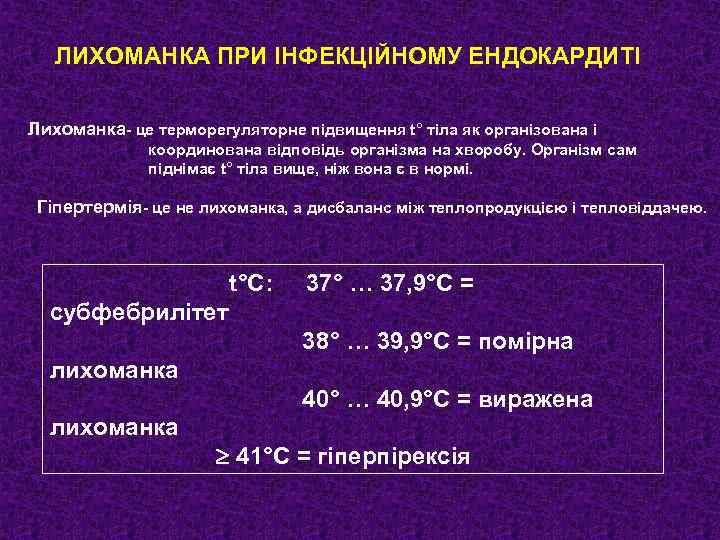

ЛИХОМАНКА ПРИ ІНФЕКЦІЙНОМУ ЕНДОКАРДИТІ Лихоманка- це терморегуляторне підвищення t° тіла як організована і координована відповідь організма на хворобу. Організм сам піднімає t° тіла вище, ніж вона є в нормі. Гіпертермія- це не лихоманка, а дисбаланс між теплопродукцією і тепловіддачею. t°С: 37° … 37, 9°С = субфебрилітет 38° … 39, 9°С = помірна лихоманка 40° … 40, 9°С = виражена лихоманка 41°С = гіперпірексія